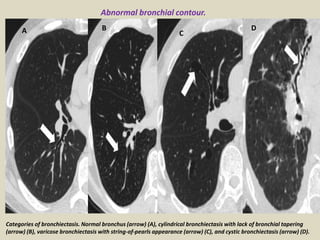

Categories of bronchiectasis. Normal bronchus (arrow) (A), cylindrical bronchiectasis with lack of bronchial tapering

(arrow) (B), varicose bronchiectasis with string-of-pearls appearance (arrow) (C), and cystic bronchiectasis (arrow) (D).

Abnormal bronchial contour.